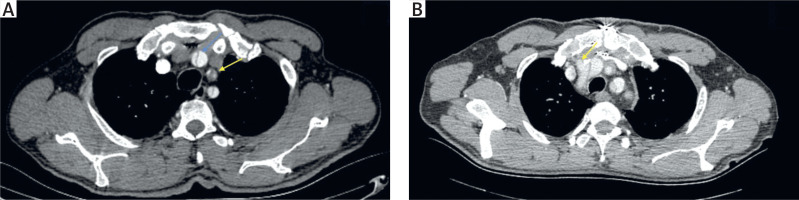

Figure 1

A – Preoperative computed tomography angiography(CTA) image showing innominate artery dissection (blue arrow) and left carotid artery occlusion with thrombi (yellow arrow). B – Postoperative CTA image of the same patient showing the innominate artery cannulation site (arrow)

The patients’ baseline demographic characteristics are summarized in Table I. Forty-six patients who underwent emergency surgical repair for ATAAD between January 2021 and April 2024 were retrospectively evaluated. ATAAD was defined as an aortic dissection (AD) detected within 14 days after the onset of symptoms. The anatomy of AD was classified according to the DeBakey classification [8]. Prior to the procedures, all patients underwent transthoracic echocardiography (TTE) performed by expert cardiologists. The radiologist and cardiovascular surgery team then performed computed tomography angiography (CTA), thoroughly examined the images, and verified the findings intraoperatively (Figures 1, 2). At presentation, dissection extent was DeBakey type I in 37 (80.4%) and type II in 9 (19.6%). The patients were grouped as those with right AXA cannulation (group 1, n = 18) and IA cannulation (group 2, n = 28). The groups were compared based on preoperative, intraoperative, and postoperative data. The GERAADA score was calculated individually for each patient using a web-based tool by a cardiovascular surgeon who was blind to the study [9]. All procedures were carried out by different surgeons using similar techniques.